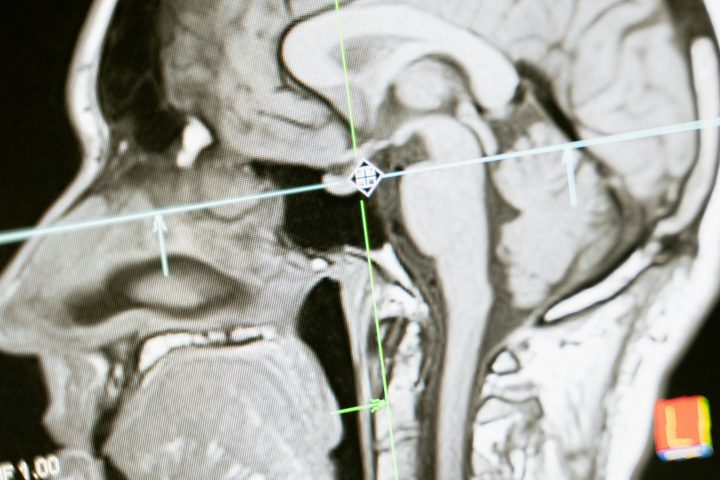

• Children can get hearing aids or cochlear implants early, giving them access to sound.